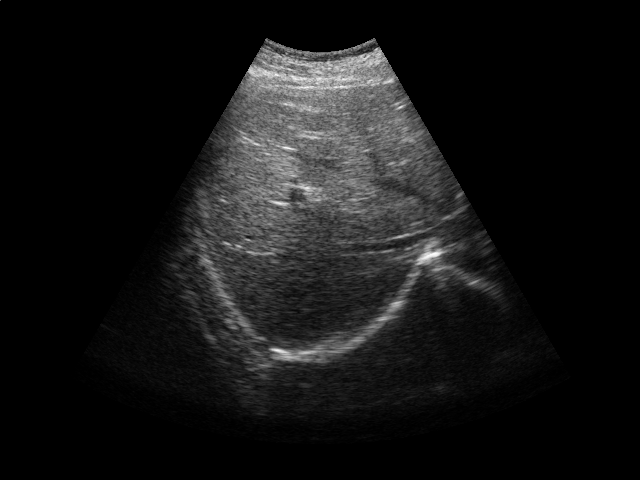

Refer to caption

Figure 2: Ultrasound gating. Top: Ultrasound images of the liver over time (abdomen, right upper quadrant). Bottom left: Correlation coefficient vs. error tolerance ε𝜀\varepsilon. Bottom right: The number of support vectors vs. error tolerance ε𝜀\varepsilon. Both figures in the bottom report results for different values of kernel ridge regression regularization parameter λ𝜆\lambda.

Respiratory gating tracks a patient’s breathing cycle, which has numerous applications such as 4D imaging, radiation therapy, and image mosaicing [16]. Manifold learning has been used for highly accurate respiratory gating of ultrasound images [23], where 4D data reconstruction was achieved with retrospective gating, i.e., the gating was calculated after the data acquisition was finished. We extend this work to attain real-time gating. A small number of breathing cycles are acquired and used as input for manifold learning to construct the respiratory signal, as is done for retrospective gating. The new incoming stream of ultrasound images is then gated by performing an out-of-sample extension.

We conduct experiments on five 2D ultrasound image sequences of the human liver acquired during free breathing; example images are shown in Fig. 2. Each sequence contains 640×\times480-pixel images and vary in length between 298 and 371 frames captured at 33 Hz. For a given image sequence, we use each image in the sequence as an input data point for learning a 1D manifold with Laplacian eigenmaps [4]; we use a 9-nearest-neighbor graph with an associated heat kernel of temperature t=10𝑡10t=10. The 1D embedding learned using an entire sequence of images serves as a reference signal for evaluating our sparse out-of-sample extension versus kernel ridge regression as the baseline. In what follows, we compare the 1D embedding of our sparse out-of-sample extension to the reference signal by computing a correlation coefficient between them. We use kernel ridge regression as a baseline method. Here we train on the first 200 frames and test on the remaining frames. We then compare the results with those obtained by training on all frames, as would be done for retrospective gating.